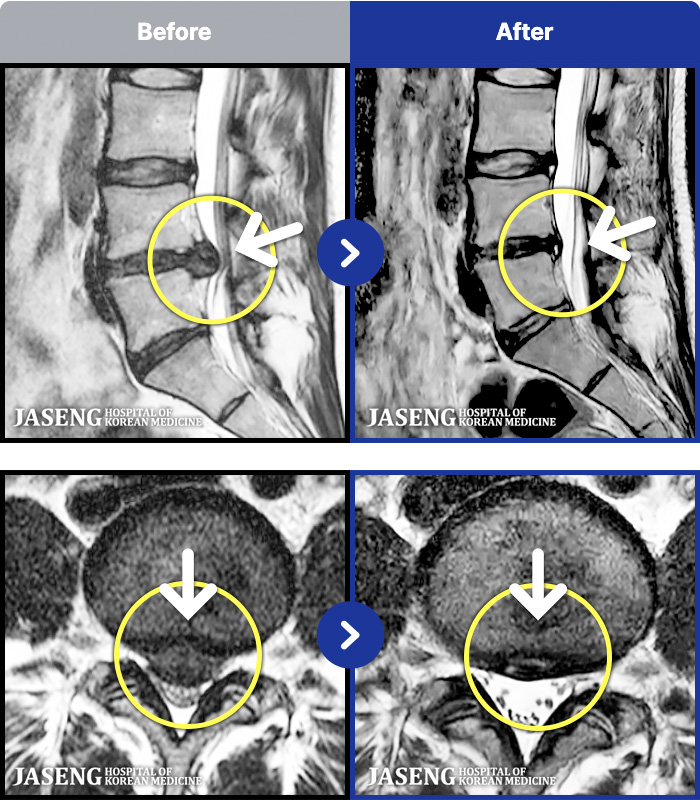

1,287 MRI ũ ʸ Ȯϼ.

[ϻ] 24.07.25~25.08.01